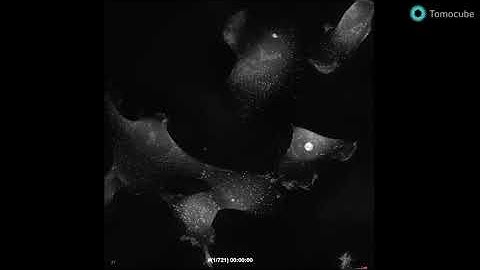

Label-free observation of neuron dynamics, taken by Tomocube Holotomography system